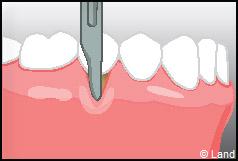

LES TECHNIQUES SANS APPORT DE GENCIVE :

Elles font appel à des lambeaux de gencive restante à proximité des récessions, qui sont déplacés et repositionnés sur la récession.

Dans ce cas le lambeau est déplacé latéralement pour combler la récession.